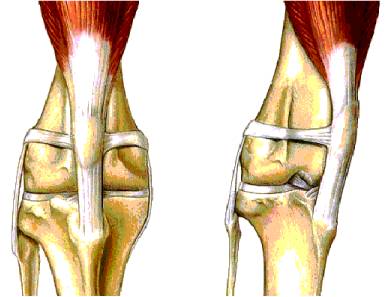

Grade 1 and early grade 2 MLP may only require medical treatment for pain and minor swelling within the knee joint. Mid-stage grade 2, grade 3 and grade 4 are best corrected with surgery. The three common surgical procedures are described as follows;

Tibial Crest Transposition (TCT). The patella tendon attaches to the top of the tibia. This area of bone is surgically separated from the shaft of the tibia and repositioned on the outside of the tibia. The bone is secured by pins and wires or a surgical screw. Recovery time to normal walking is 6-8 weeks although most dogs are weight bearing within 1 to 2 days.

Wedge Recession Trochleoplasty (WRT). The groove in the femur where the patella lies is surgically deepened by cutting out a wedge shaped section. |

Lateral ligament placement. This involves placing nylon bands through the patella and its tendon and anchoring them to the outside of the knee joint.

Any, a combination of, or all of the above techniques may be used to repair MLP. This decision is made during surgery and depends on the size of the dog, degree of luxation, conformation of the knee joint and the presence of osteoarthritis.